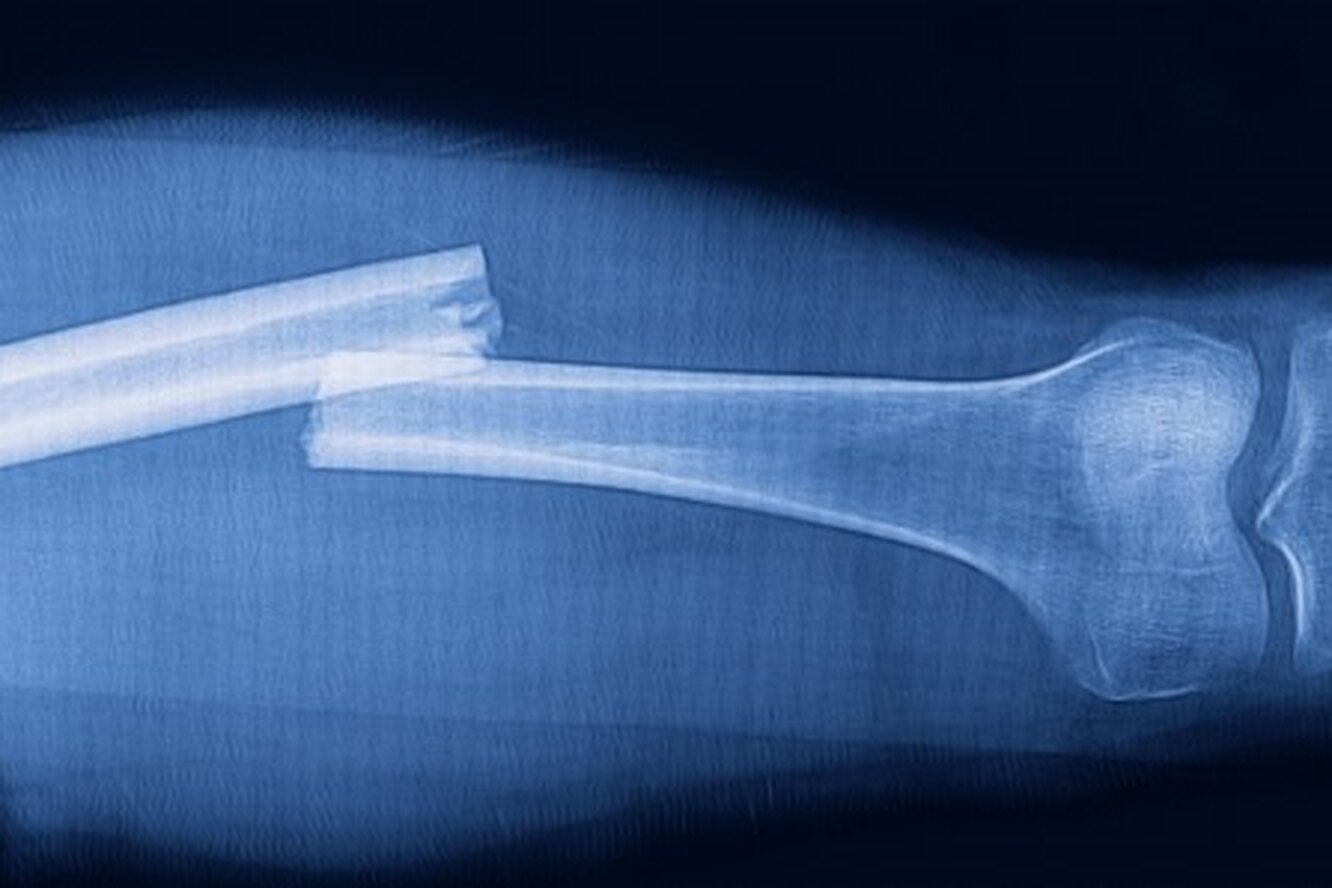

Kırıklar, kemik bütünlüğünün travma veya hastalık sonucu bozulmasıdır ve günlük yaşamı önemli ölçüde etkileyebilir. Cerrahi ya da konservatif tedaviyle kemik iyileşmesi sağlansa da, esas işlevselliğin yeniden kazanılması rehabilitasyon süreciyle mümkündür. Kırık sonrası fizyoterapi, hem kas gücünü hem eklem hareket açıklığını yeniden kazandırmayı hedefler. Bu süreçte robotik teknolojilerle desteklenen rehabilitasyon, iyileşmeyi hızlandırır ve hasta motivasyonunu artırır. Robotik Rehabilitasyon Merkezimiz, bu alandaki yenilikçi uygulamalarıyla hastalarımıza güvenli ve etkili bir iyileşme süreci sunmaktadır.

Kırıklar, genellikle travma (düşme, çarpma, trafik kazası gibi) sonrası meydana gelir. Ancak osteoporoz gibi kemik yapısını zayıflatan hastalıklarda daha düşük şiddetli travmalar bile kırığa yol açabilir.

Kırığın tipi, yeri ve şiddeti, uygulanacak rehabilitasyon programının şekillenmesinde belirleyici rol oynar.